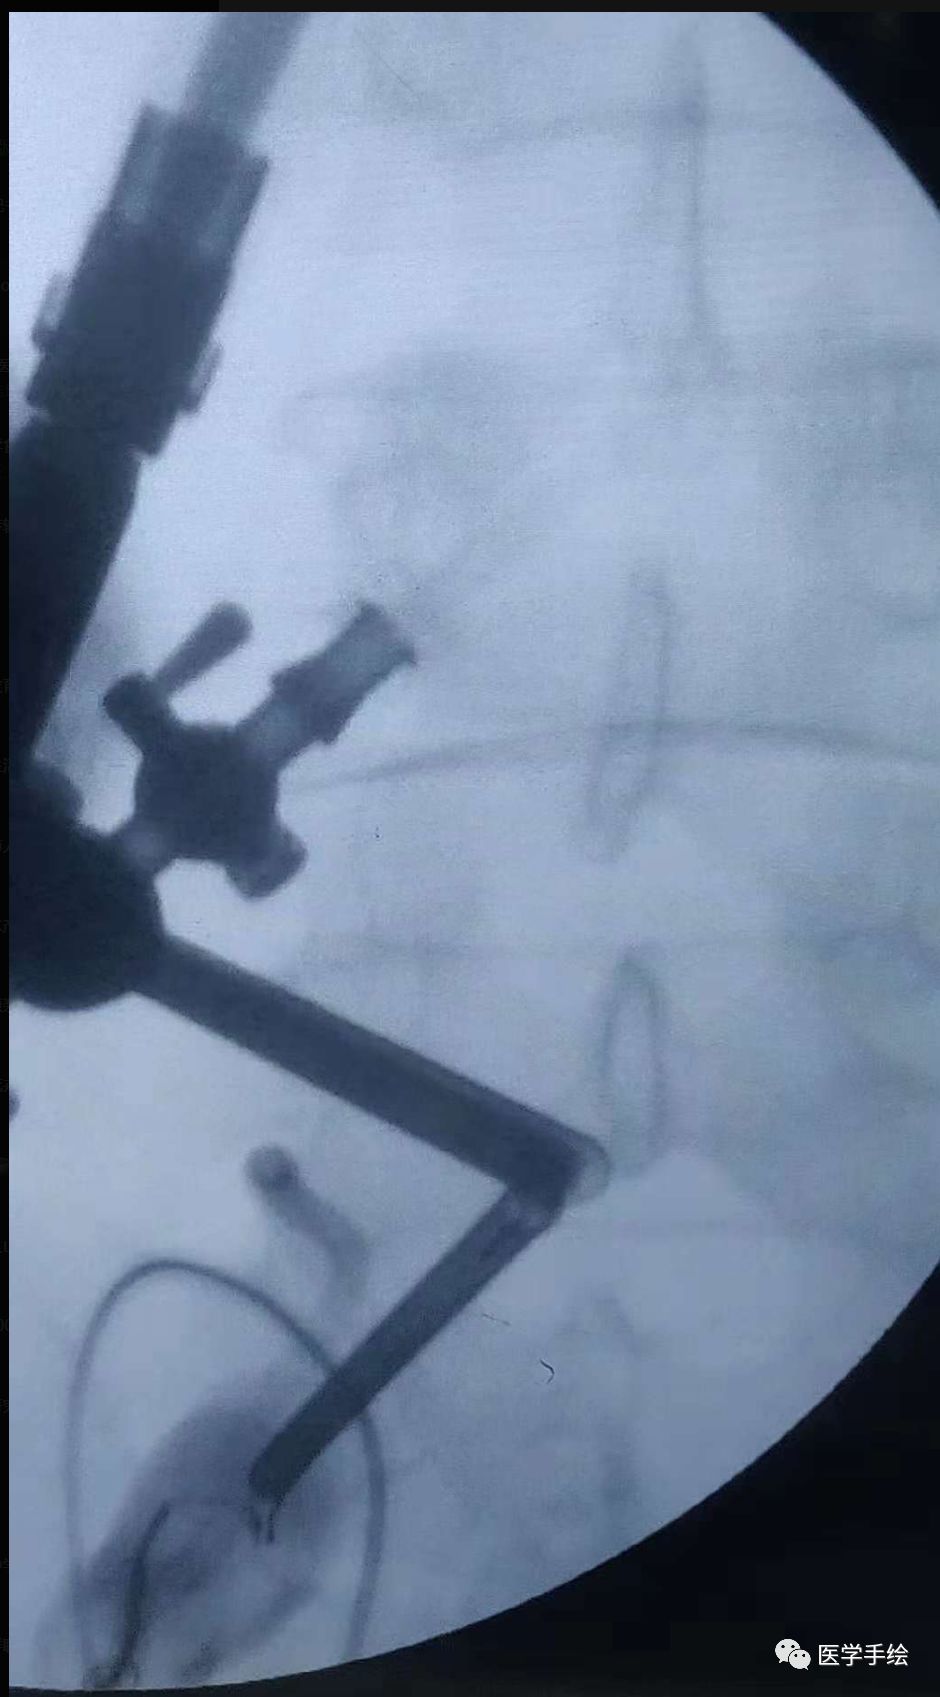

1、首先透视确定观察通道(view)及工作通道(work)的体表位置。很多人选择病变间隙中线的上下1cm处作为两个通道的定位点,本病例选择了L5椎板下缘及S1椎板上缘分别作为V通道及W通道的定位点。如果术者站在患者左侧一般左手持关节镜,右手持操作器械,站在右侧则相反,以此决定两个通道的上下位置。